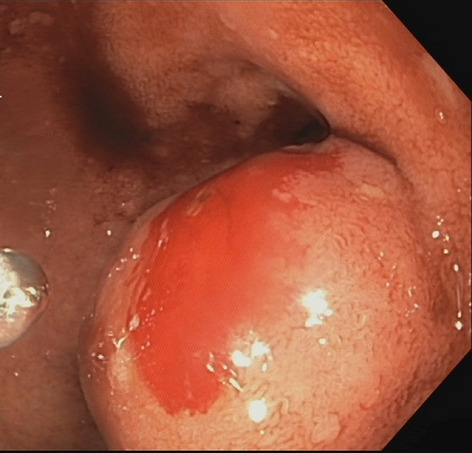

Result: The comparative analysis of the data shows a decrease in the number of presentations in ESU of AC cases during the pandemic, compared to the previous year, most often due to patients' fear of contacting the virus in the hospital environment. The median time between the onset of symptoms and the presentation in the ESU: 2020 – 14 days, 2019 – 5 days. Forms of moderate and severe AC predominated in the pandemic: GradeI—14.28%; GradeII—57.14%; GradeIII—28.57%. In 2019 GradeI—66.39%, GradeII—27.73%, GradeIII—5.88%. Laparoscopic cholecystectomy was attempted for all patients from the beginning, but the complications identified during surgery and severe forms led to a conversion rate in 2020 of 14.28%, compared to 5.88% in 2019. The severity of the cases is also observed in the postoperative complications encountered (perihepatic abscess Fig. 2. Figure 2, wound infection, bile leak; 2019—5.04%, 2020—23.21%), which required surgical reinterventions to solve them (2019: 2.52%, 2020: 10.71%). The number of deaths was significantly higher in 2020 (5.35%), compared to 2019 (0.84%).